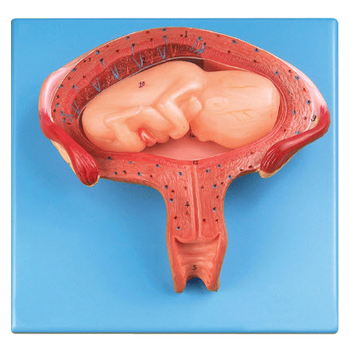

GD/A42005/7七個月胎兒模型產品介紹:1、尺寸:自然大,高25cm,寬14cm,厚8.5cm,共有14個部位指示標志。2、材質:進口PVC材料、進口油漆、電腦配色、高級彩繪有關GD/A4200...